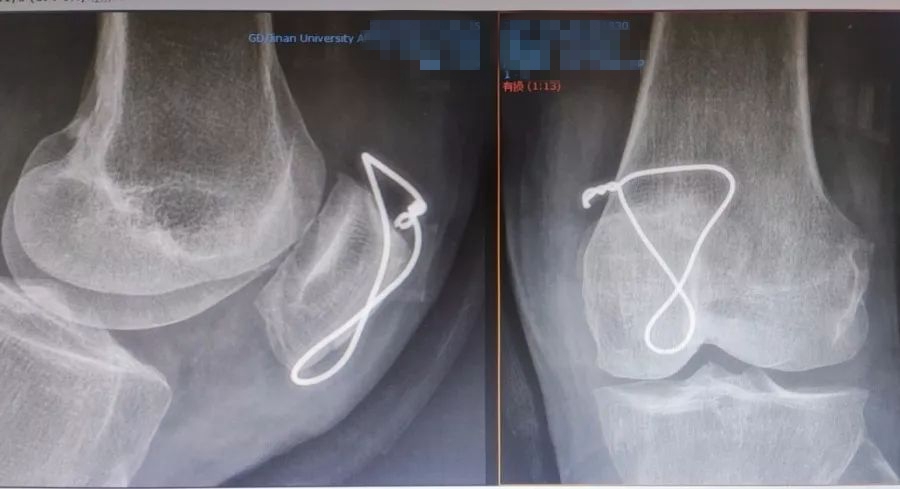

尽管现有克氏针、记忆合金髌骨爪等内固定方法,但暨南大学附属第一医院骨关节运动医学中心继承查振刚教授的环扎+"8"字张力带钢丝固定。这种内固定的方法, 操作简单,效果满意,适用于各种类型髌骨骨折,尤其是治疗髌骨粉碎性骨折更有其优越性。随着关节镜微创技术发展,科室的关节镜下经皮微创张力带钢丝内固定已有开展。

环扎+"8"字张力带钢丝固定

采用关节镜的辅助,可以监视髌骨关节面的软骨复位情况,探查关节内其他部位软骨、半月板、交叉韧带的情况并对关节内积血进行清理。关节镜监视下确认钢丝出入髌腱、股四头肌腱的软组织层面,监视下进行张力带钢丝的收紧,可更好地评估关节面软骨稳定及平整程度,更好地指导术后康复强度和进度。